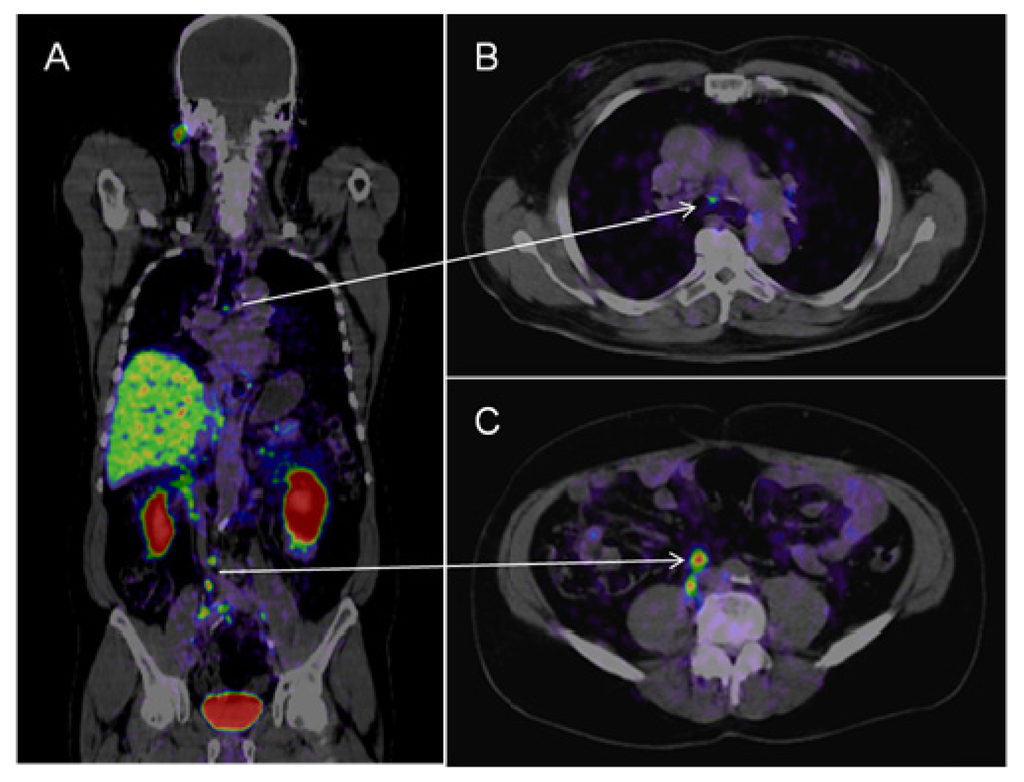

Figure 1.

18F-choline PET-CT. Patient after radical prostatectomy with slowly increasing PSA (current PSA: 1.5 μg/L). The figure shows series of native CT images (A); PET images 60 min after the administration of 18F-choline (B) and fused PET-CT images (C) in transversal, sagittal and coronal views. The PET images show a small hot spot in the right inguinal region with increased isotope uptake. In the PET-CT fused images this spot can be identified as a small right inguinal lymph node highly suspect for a metastasis. (F: Transverse plane; L: Saggital plane; A: Coronal plane).